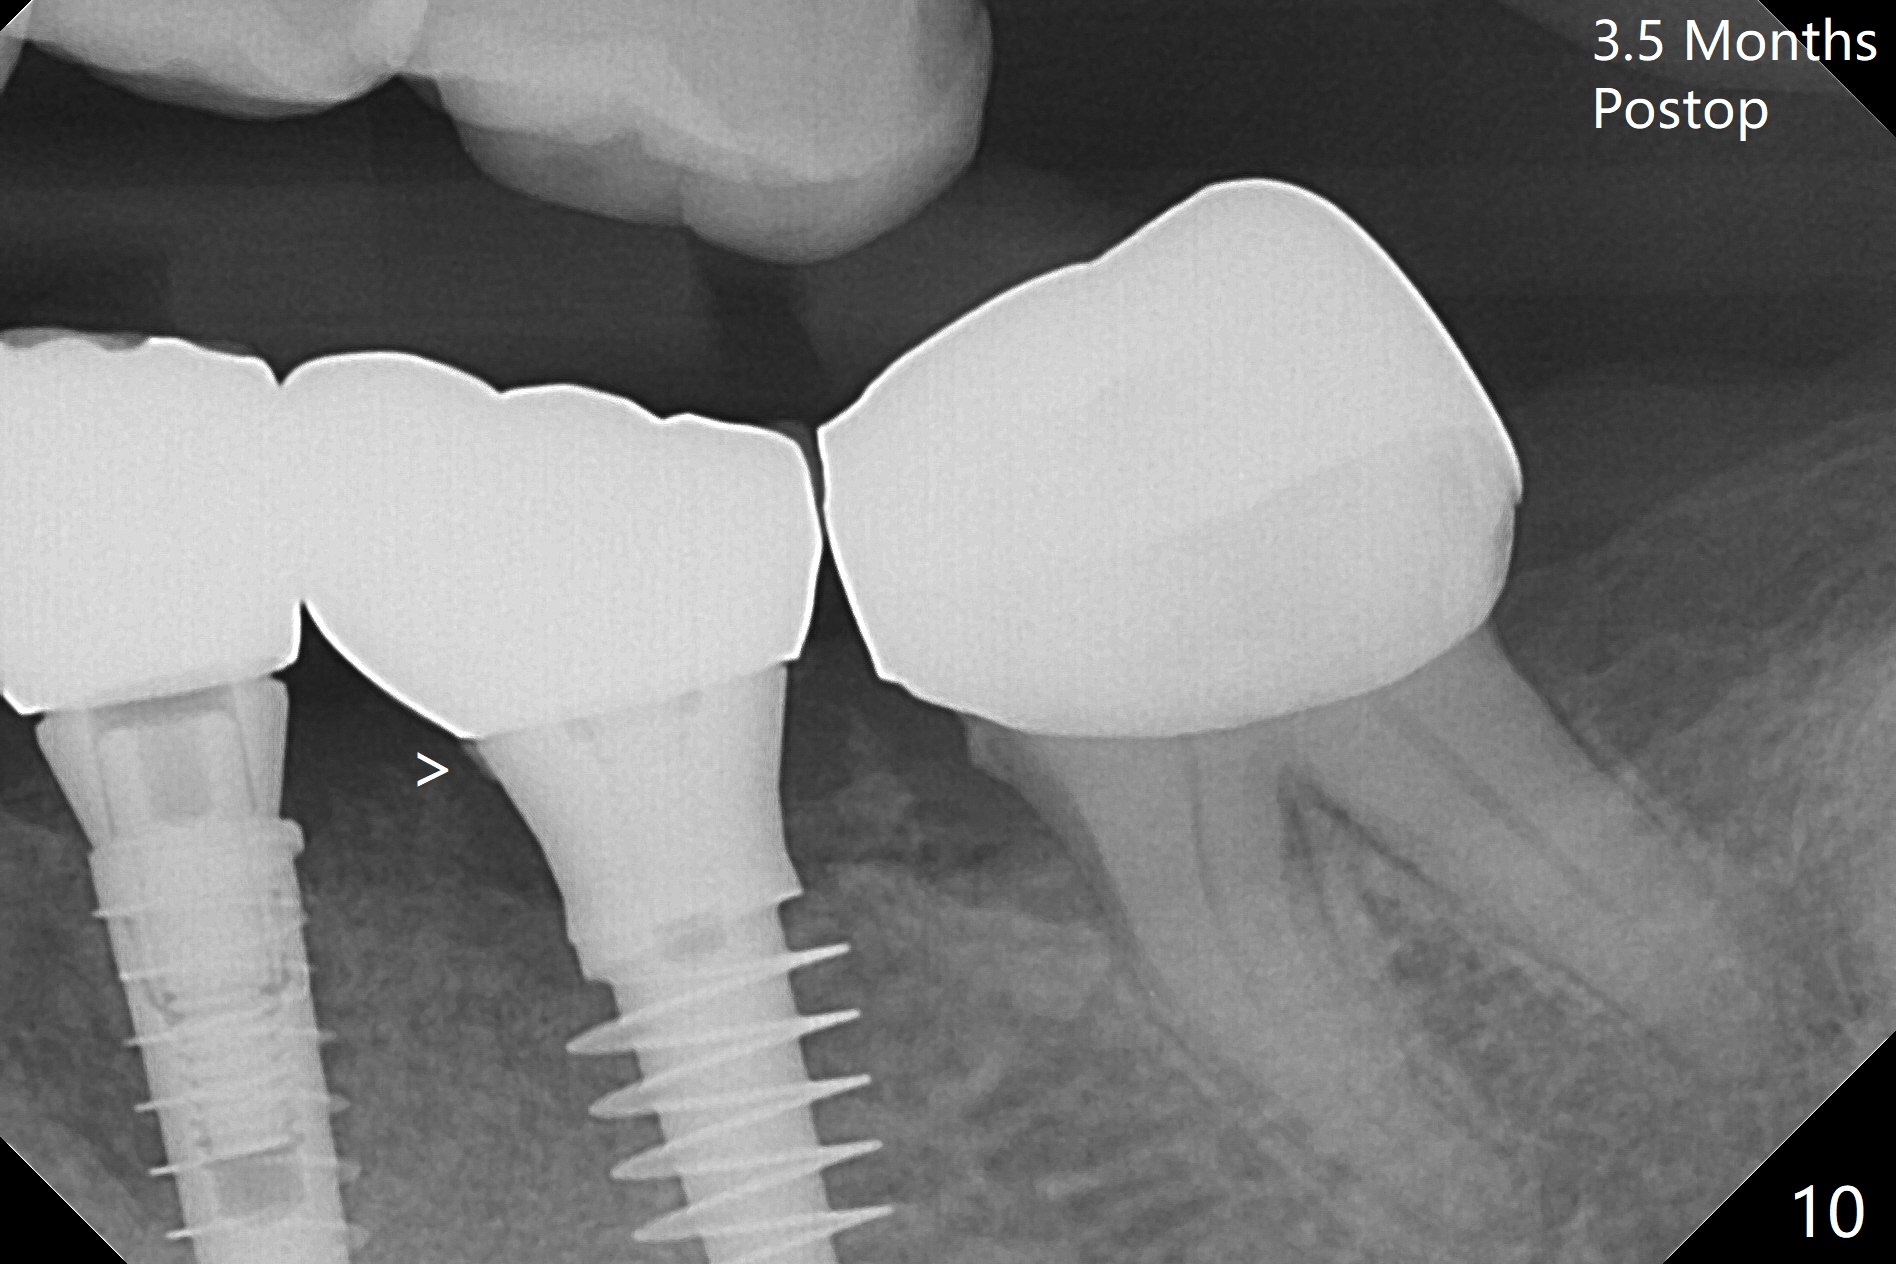

There is no bone loss at #20 or 19 six and 3 months postop, respectively (Fig.6,7). After placing and trimming a 4.3x3 mm Magicore solid abutment, impression is taken (Fig.8). After cementation for #19 and 20 crowns, the crown of #20 is removed for cement removal; attention is paid to cement removal around the crown at #19. In fact, the removal is ineffective with the crown of #20 is reseated and retightened (Fig.9 >). Repeated removal proves to be futile (Fig.10 >). The most effective method will be to take X-ray immediately after #20 crown removal and reseating without torque so that it will be easier to remove the remaining cement if needed. It may be ok in term of hygiene, since proximal brush is used daily. While the crowns at #18 and 19 are being redone because of food impaction, the tooth #18 needs RCT; the Magicore seems to have no bone loss 4 months post cementation (Fig.11). CBCT shows that the Magicore seems to have been placed in the middle of the crest 7 months post cementation (Fig.12 (B: buccal)). The gingiva at #19 is apparently healthy 8 months post cementation. The crown at #19 is recemented 10.5 months post cementation (Fig.13).